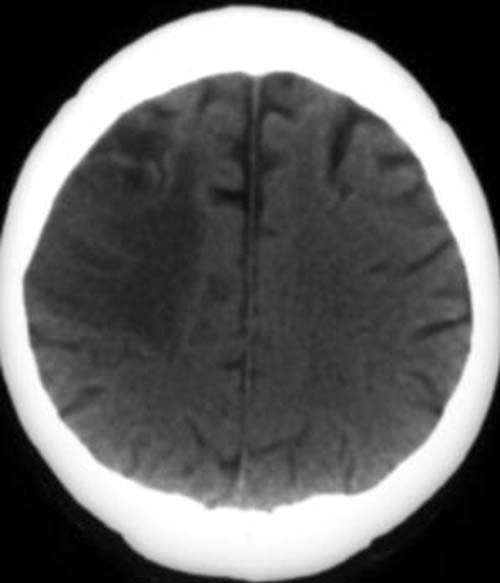

Patient, 58 Jahre alt mit Halbseitenlähmung links.

CCT nativ (ohne Kontrastmittel).

Hypodenses Areal hochfronto-parietal rechts. Konturunschärfe der Rindenmarkgrenze rechts.

Nicht ganz frischer Mediateilinfarkt rechts (4-7 Tage).